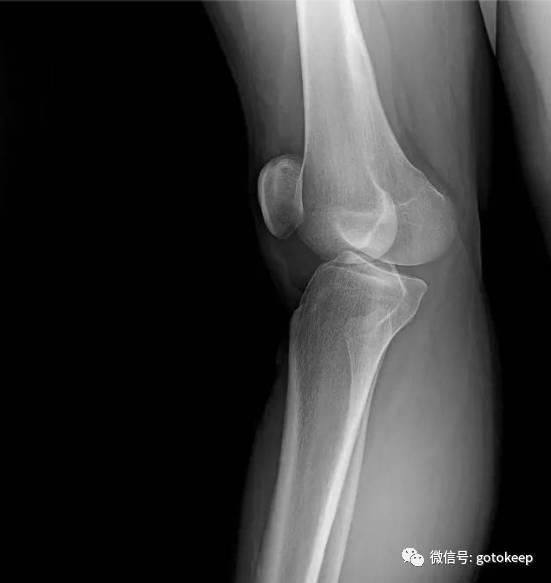

这是一张膝关节超伸的 X 光片,图中很明显地看到关节前侧的缝隙变得很窄,髌骨与股骨(大腿骨)之间的缝隙也很窄。

正常情况下,两个骨头应该是在「关节面」均匀接触的,重力会平均分布在整个支撑面上。但超伸之后,就全压在关节前侧了。这些现象很有可能成为膝关节病痛的诱因。如果髌骨和股骨之间还可能会有摩擦,那就更糟糕了。